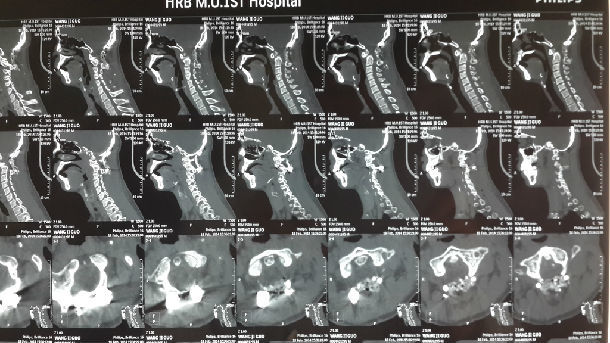

术后寰枢椎复位,植骨融合,ADI小于2mm